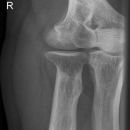

Ellenbogen ventro-dorsal (1. Ebene a.-p.)

Abbildungskriterien

distale Humerunsanteile: Epikondylen, Capitulum humeri

proximale Unterarmanteile: Radius-Radiusköpfchen und -hals, Ulna -Schaft, Körper, Olecranon

Qualitätskriterien

Ellenbogengelenk vollständig a.p. orthograd abgebildet, Gelenkspalt in Filmmitte und überlagerungsfrei.